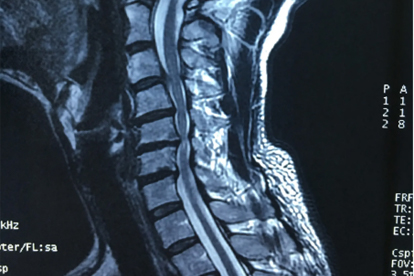

颈椎疾病多由长期不良姿势、颈椎退行性变或外伤引起,常见症状包括颈部疼痛、头晕、上肢麻木等。早期诊断和治疗对缓解症状、防止病情恶化至关重要。